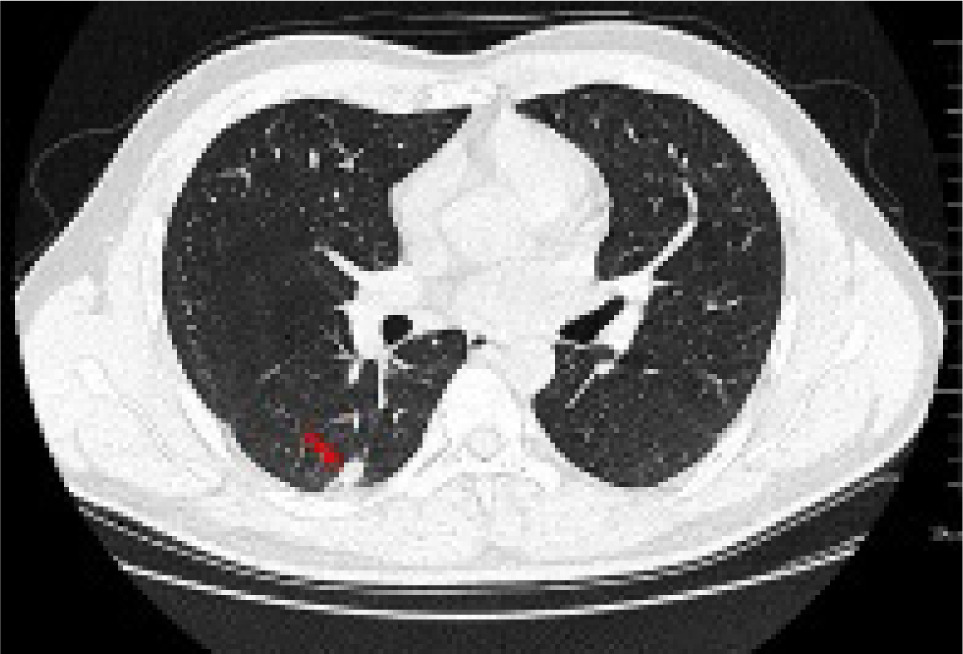

Further examinations were conducted upon admission (Table 1). A chest CAT (CT) scan conducted on January 15, 2021 suggested a possible pulmonary infection with a shadow measuring approximately 19×9 mm in the right lower lobe (Figure 1).

Figure 1: Lung CT shows that there is a calabash type density increase in the dorsal segment of the lower lobe of the right lung, the size of which was about 19×9 mm (red arrow).